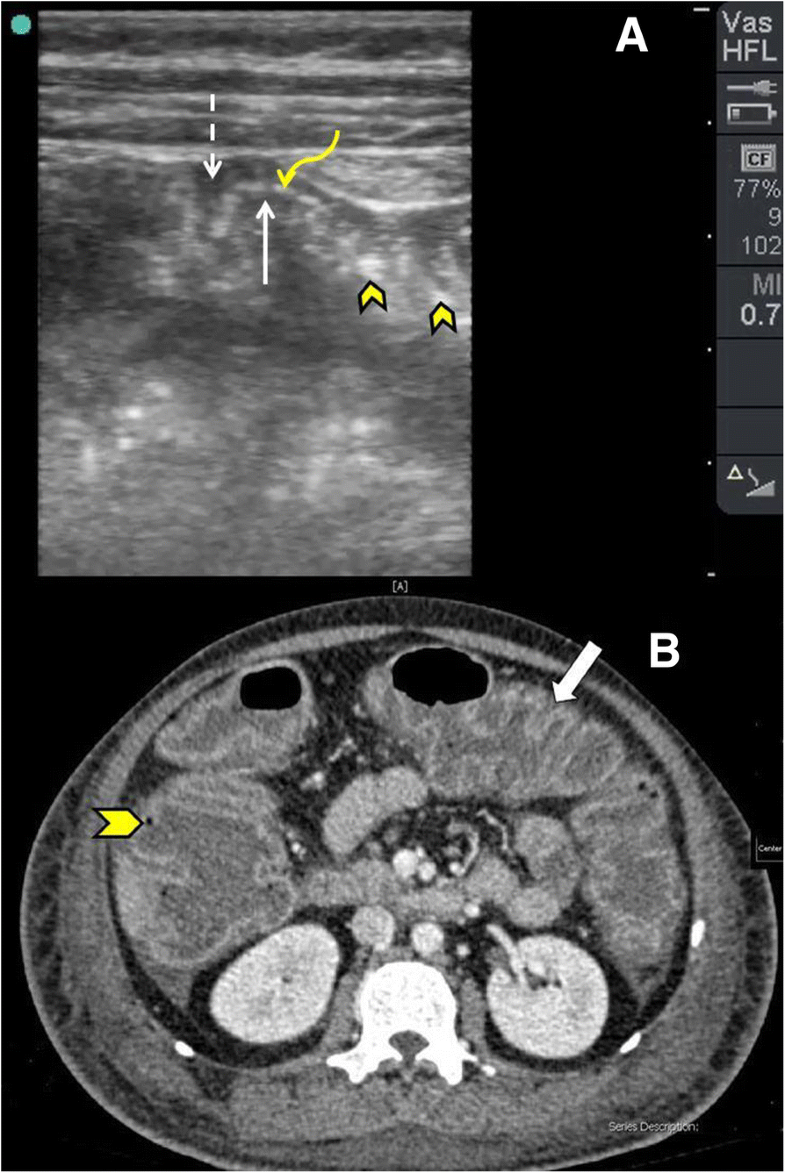

From www.eurorad.org

The accordion sign in chronic alcoholic liver disease Eurorad Accordion Sign The accordion sign is seen on ct images of patients with oral. To determine whether the “accordion sign” is a specific computed tomographic (ct) sign of clostridium difficile. Pseudomembranous colitis with yellow pseudomembranes seen on the wall of the sigmoid colon. Another indicator of colitis in ct scans is the “accordion” sign. Clostridioides difficile colitis, also known as pseudomembranous colitis. Accordion Sign.

The accordion sign in chronic alcoholic liver disease Eurorad Accordion Sign The accordion sign is seen on ct images of patients with oral. White oval highlights markedly thickened bowel wall with oral contrast trapped between haustral folds in a patient with. The accordion sign is a ct or radiographic appearance of the colon, resembling a musical instrument, in cases of pseudomembranous. Another indicator of colitis in ct scans is the “accordion”. Accordion Sign.